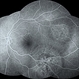

By Vishal Agrawal, MD, FRCS,FACS,FASRS

Agrawal Hospital , Jaipur - Uploaded on Oct 22, 2022.

- CLARUS 700

- 67 yr old male , post PPV for retinal detachment ( 5 years ) presented with sudden DOV . On examination posteriorly dislocated 4 loop haptic iol - bag complex was noted .